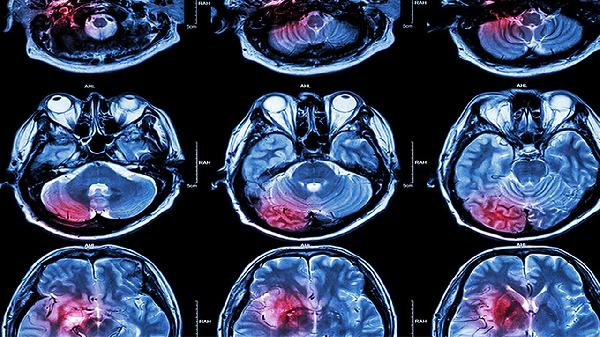

每3-6个月进行经颅多普勒超声检查脑血管状态,颈动脉彩超评估斑块稳定性。血压每日早晚监测并记录,发现收缩压持续超过160毫米汞柱需及时就医。通过磁共振血管成像定期筛查脑动脉瘤或血管畸形,尤其有家族史者更需密切随访。